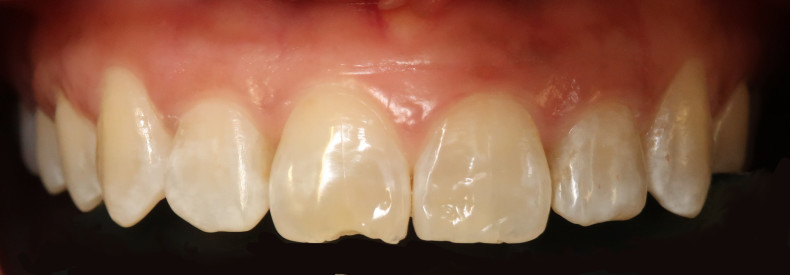

Der intraorale Befund (Abb. 2a–e) sowie die Modellanalyse (Abb. 3a–e) zeigten neben dem Diastema mediale im Oberkiefer vor allen Dingen eine Anteinklination und Supraokklusion beider Fronten. Besonders anterior wiesen beide Zahnbögen eine transversale Enge auf. Dies zeigte sich in einem deutlichen Unterkieferfrontengstand mit Labialkippung des Zahnes 41. Neben Abrasionen und Schlifffacetten, vor allem in der Front, waren auch vereinzelt Gingivarezessionen erkennbar. An Zahn 11 lag eine Schmelzfraktur der Inzisalkante vor. Durch die zwangsgeführte Laterognathie ergab sich eine Mittellinienverschiebung nach rechts von 3 mm. Eine beidseitige Distalokklusion bei vergrößerter sagittaler (6 mm) und vertikaler (5 mm) Stufe war erkennbar. Aufgrund der deutlichen transversalen Zahnbogenenge im Unterkiefer ergab sich links eine Tendenz zum Scherenbiss.